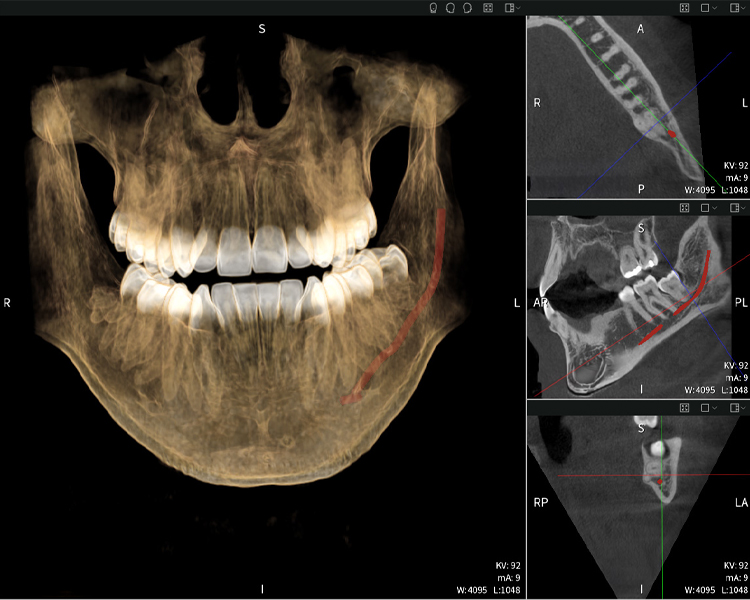

Figura b: Resultados de imagen de Seethrough Max, sobre un fondo negro.

Las figuras b–d muestran varias vistas de una reconstrucción 3D de la mandíbula, proporcionando una visión general completa de la anatomía mandibular, la posición de los nervios en relación con los dientes y permitiendo evaluar la simetría y alineación dentaria.

La figura d muestra el diente 48 previamente tratado, con la corona retirada y las raíces dejadas en proximidad al nervio, lo que ilustra el alto riesgo de daño nervioso.